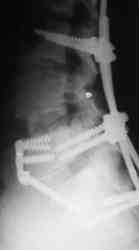

Если позволите, некоторые теоретические соображения по результатам и показаниям. Сегодня все знают как оперировать позвоночник по поводу любых "напастей". Когда после операции боли остаются приходит время вспомнить о том, что морфологический субстрат боли при полисегментарной саногенетической реакции патологического типа, каким является остеохондроз и другие спондилогенные изменения дегенеративно-дистрофического характера, точно установить, как правило, невозможно. Аномалиям развития здесь особенно не повезло. Например, если у пациента протрузии на нескольких уровнях, дегенеративный стеноз и сакрализация - лечат сакрализацию т.к. она "режет глаз" специалисту. Соответственно и эффект от вмешательства на уровне "не навредили". Специальные методы исследования мало что дают в этом плане, а МРТ, вообще, годится только для обоснования необходимости операции при разборе жалобы. Поэтому вначале рекомендую лечебно-диагностические тест-блокады. Если эпидуральная по Катлену через день (результат оценивать после 3-5 блокад) снимает жалобы - оперировать не стоит. Если локальная боль остается - прицельную паравертебральную в зону неоартроза - исчезновение боли показание не к операции, а к повторному курсу через 3-6 мес. Стойкий локальный монолатеральный болевой синдром - повод задуматься об операции. Но, как правило, она должна быть более обширной чем просто резекция поперечного отростка и санировать и другие проблемы. "Золотой стандарт" тут пока передне-задняя фиксация в различных ее вариантах в зависимости от конкретного случая. Попытки "располовинить" спондилодез в отношении чистой изолированной транспедикулярной фиксации в пятилетнем наблюдении не выдерживают критики. Передняя изолированная фиксация пластинами с аутокостным спондилодезом дает хорошие результаты (пример на фото 4) при условии дополнения задним релизом для декомпрессии сосудисто-нервных образований ( ну а тогда почему уже и конструкцию сзади не поставить? фото 5).

Имя     : Комбинированный спондилодез.JPG

Url     : http://weborto.net:8080/pipermail/ortho/attachments/20070705/09230b3f/attachment-0005.jpeg